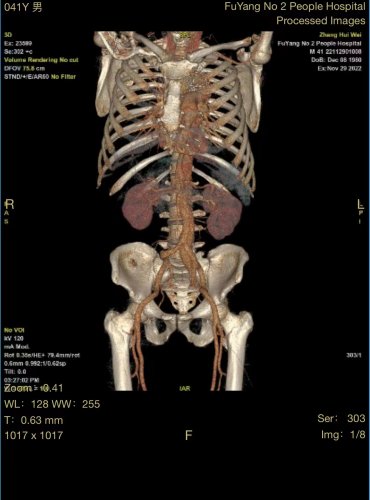

患者张某,男性,41岁,颍州区九龙镇居民,2020年因主动脉夹层在市第二人民医院血管外科行胸主动脉覆膜支架腔内隔绝术,术后恢复尚可,1月前在进行重体力劳动后,出现腰背部疼痛不适,复查主动脉CTA,考虑腹主动脉夹层动脉瘤。

由于患者手术情况复杂,血管外科团队与介入导管室、麻醉科等积极沟通并进行充分的手术准备,在多学科相互配合下,为患者行腹主动脉覆膜支架置入及“四开窗”术,手术顺利,完美隔绝夹层破口,保留腹腔干、肠系膜上动脉、双肾动脉,患者恢复良好。